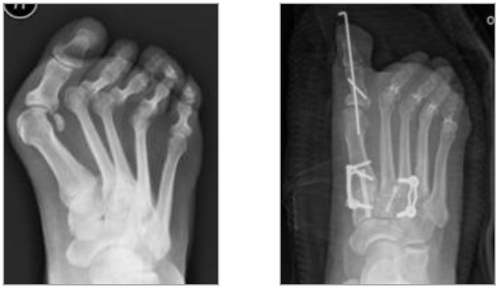

CASE STUDY

This patient required extensive surgery to correct a severe bunion and lesser toe deformity with mid foot arthritis.

The wire in the great toe was removed a few weeks after surgery. The patient had similar surgery on the other foot where the operation resolved a long history of severe foot pain.